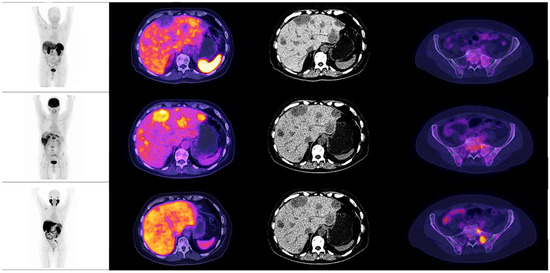

Figure 8. Patient number 3, a 77-year-old male, with an initial histopathological report of prostate adenocarcinoma, Gleason score 9 (4 + 5). Treated with androgen deprivation therapy + chemotherapy. Site of second biopsy was in left iliac bone, with a confirmatory histopathological report of neuroendocrine carcinoma (positive immunohistochemistry for chromogranin and synaptophysin). Time lapse to neuroendocrine differentiation was 48 months, with a PSA value of 0.003 ng/dL at the time of diagnosis. The image shows the maximum intensity projection of the three radiotracers (18F AlF-NOTA-Octreotide, 18F–FDG and 18F–PSMA-1007) with multiple lung nodules, a single liver metastasis and osteoblastic lesions with high glycolytic metabolism in molecular imaging. 18F–PSMA-1007 and 18F AlF-NOTA-Octreotide PET/CT showed diffuse uptake of the radiotracer in described lesions.

When observing the lesions and the percentage of uptake by a semi-quantitative assessment, which was determined by SUVmax for each radiopharmaceutical, it was found that the positive uptake of 18F–PSMA-1007 is greater at bone lesions, lymph node and seminal vesicles compared with the other radiotracers. Conspicuously, FDG was identified as the best radiotracer for the overall identification of lesions, with an outstanding detection of visceral metastases (see Figure 2 and Figure 3).

The analysis revealed that the mean SUVmax for 18F-FDG was 6.4 (IQR 4.9–9.3), 6.75 for 18F–PSMA-1007 (IQR 4.5–9.4) and 4.6 for 18F AlF-NOTA-Octreotide (IQR 2.8–4.4) (see Figure 8 and Figure 9).